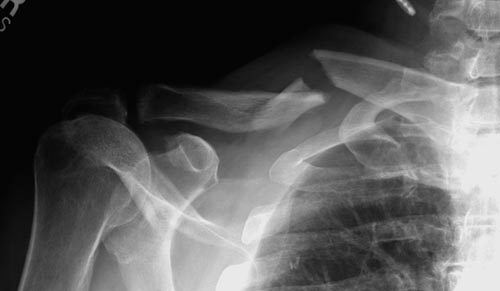

Болезненные ложные суставы надо оперировать, и здесь представлен случай

свежего болезненного ложного сустава, оперированного через 4 месяца.

Освобожден средний фрагмент и боковая компрессия лагированием, фиксация

пластиной..